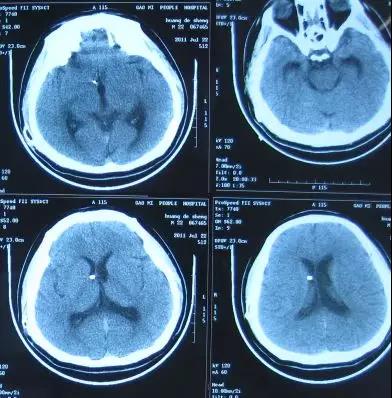

医生给予保守治疗十余天后症状仍无改善,2011年8月30日进行了第2次左侧脑室-腹腔分流术,术后第2天即2011年9月2日,症状改善,可以简单言语和活动,头部CT示脑室缩小(图-4)。

图-4:2011年9月2日头部CT